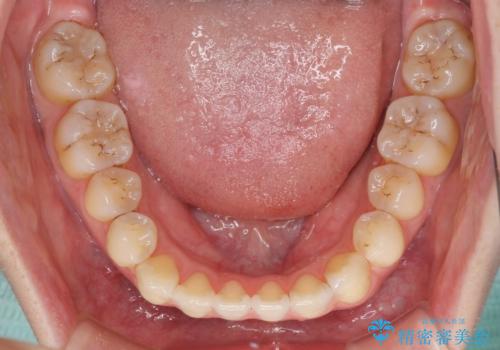

オープンバイトのインビザラインを用いた再矯正

オープンバイト(前歯の開咬)と下顎骨の偏位による不正咬合が認められました。

オープンバイトは後戻りを起こしやすいため、極力そのリスクを軽減するため、奥歯を圧下させるように治療を進めていきました。

下顎骨の偏位が顕著であったため、上下の正中を合わせることはできませんでしたが、患者様には大変満足していただきました。